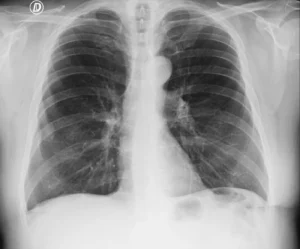

Radiografía de tórax en proyección anteroposterior (AP), obtenida en la cama del paciente, en decúbito supino, con inspiración subóptima. La segunda radiografia se obtuvo en proyeccion PA con el paciente de pie, observandose la silueta cardiaca de tamaño normal.

Este caso ilustra el aparente aumento del tamaño de la silueta cardíaca observada en la radiografía de tórax obtenida en decúbito supino, en una proyección qué necesariamente es anteroposterior (AP).

En la proyección AP, especialmente en pacientes encamados, la silueta cardíaca se encuentra más alejada del detector, lo que produce una magnificación aparente del tamaño del corazón. Este efecto geométrico puede simular cardiomegalia en ausencia de un aumento real del tamaño cardíaco.

La cardiomegalia aparente en una radiografía de tórax en proyección anteroposterior no debe interpretarse de forma aislada como aumento real del tamaño cardíaco.